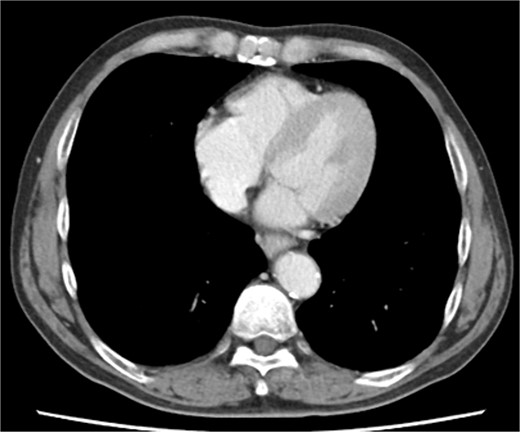

Biopsy confirmed the diagnosis of squamous cell carcinoma. Contrast-enhanced computed tomography (CT) showed wall thickening in the lower thoracic esophagus. No enlarged lymph nodes and distant metastases were found. There was no evidence of pericardial effusion, or significant coronary aneurysm (Fig. 1). No abnormal findings were observed on 12-lead electrocardiography or echocardiography. Spirometry revealed obstructive ventilatory impairment, and thus, long-acting beta-agonist and muscarinic antagonist inhalation were initiated.

Preoperative contrast-enhanced computed tomography shows no evidence of pericardial effusion, or significant coronary aneurysm.